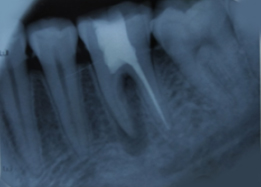

Pre-OP IOPAR

Hemisectomy